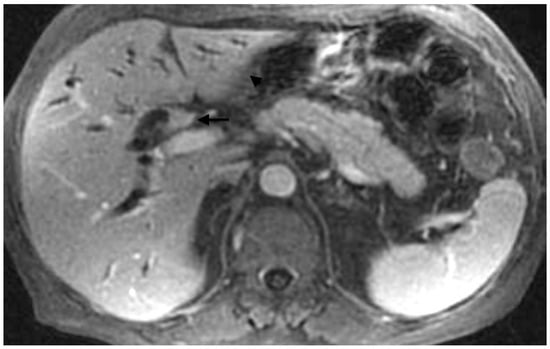

- Vienne, A.; Hobeika, E.; Gouya, H.; Lapidus, N.; Fritsch, J.; Choury, A.D.; Chryssostalis, A.; Gaudric, M.; Pelletier, G.; Buffet, C.; et al. Prediction of drainage effectiveness during endoscopic stenting of malignant hilar strictures: The role of liver volume assessment. Gastrointest. Endosc. 2010, 72, 728–735. [Google Scholar] [CrossRef] [PubMed]

- Takahashi, E. Biliary drainage strategy of unresectable malignant hilar strictures by computed tomography volumetry. World J. Gastroenterol. 2015, 21, 4946–4953. [Google Scholar] [CrossRef] [PubMed]